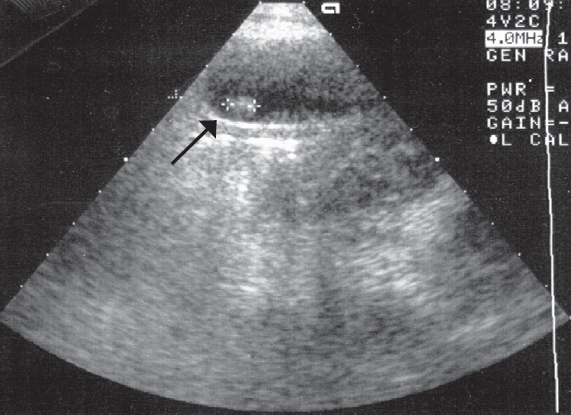

Аналогичные изменения пузырного протока были выявлены и во время проведения оперативного лечения (рис. 5). Ни у одного пациента не было найдено конкрементов во внепеченочных желчных ходах.

Рис. 5. Интраоперационная картина деформированного пузырного протока

Fig. 5. Intraoperative picture of deformed cystic duct

При детальном патогистологическом исследовании во всех случаях удаленный желчный пузырь имел признаки хронического воспаления и в подтверждении данных УЗИ — деформацию или сужение пузырного протока различной протяженности.